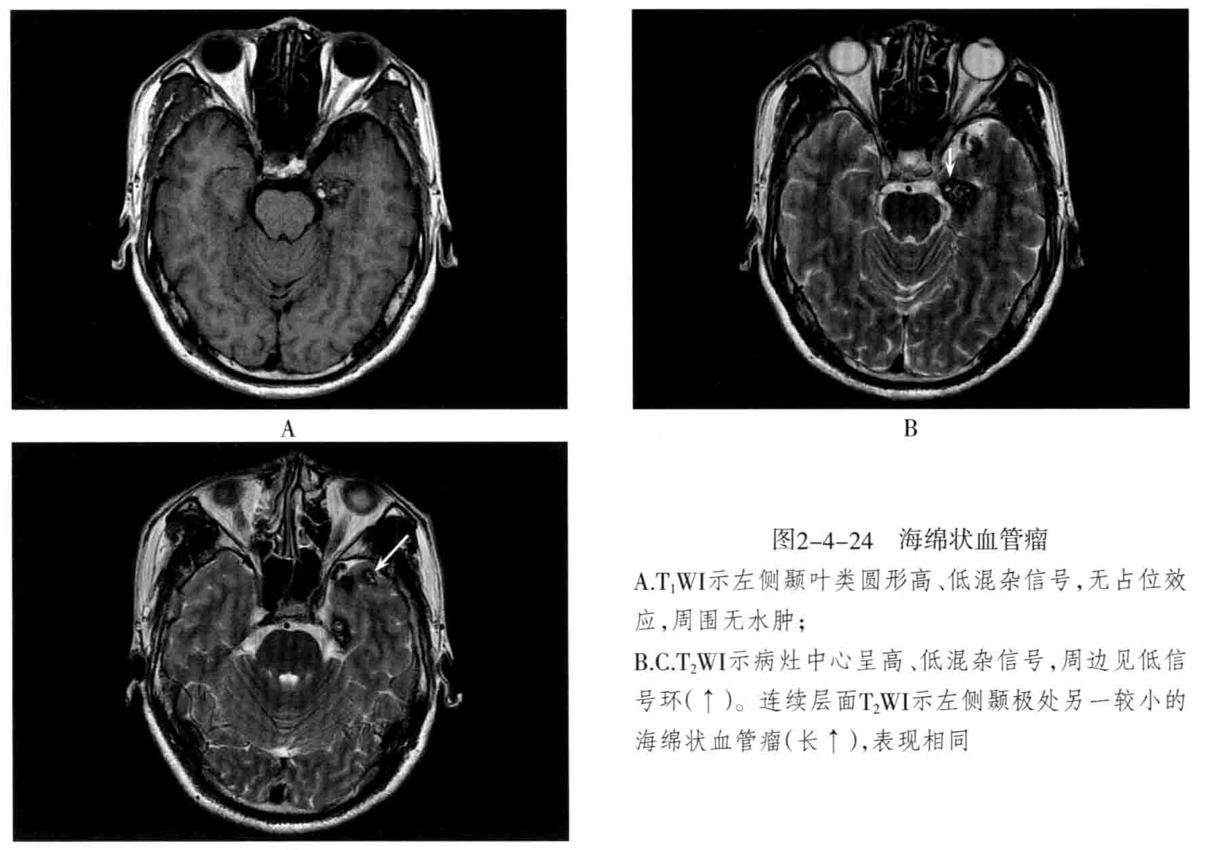

• 海绵状血管瘤 病变主要由不规则、大小不等的薄壁海绵状血窦组成,其间有增生的胶质组织,没有正常的神经组织,可反复少量出血,常有不同程度的钙化和含铁血黄素沉着。可发生于脑内(常见于大脑半球各叶)、脑外(常见于颅底)。常无任何症状,或表现为癫痫等。

3. MRI检查:T1WI多呈高信号、稍高信号或混杂信号,T2WI上呈高、低混杂信号,典型者呈“爆米花”状,境界清楚,病灶周围有含铁血黄素沉积,T2WI是表现为低信号环。病灶内及周边无流空血管影。病灶无占位效应,周围脑组织无水肿。大量出血时,表现为病灶短期明显增大,可有占位效应。增强后脑内者病灶可轻度强化,亦可无强化。脑外者多于颅底鞍旁,T1WI低信号,T2WI明显高信号,边界清楚,增强后明显强化且强化均匀。